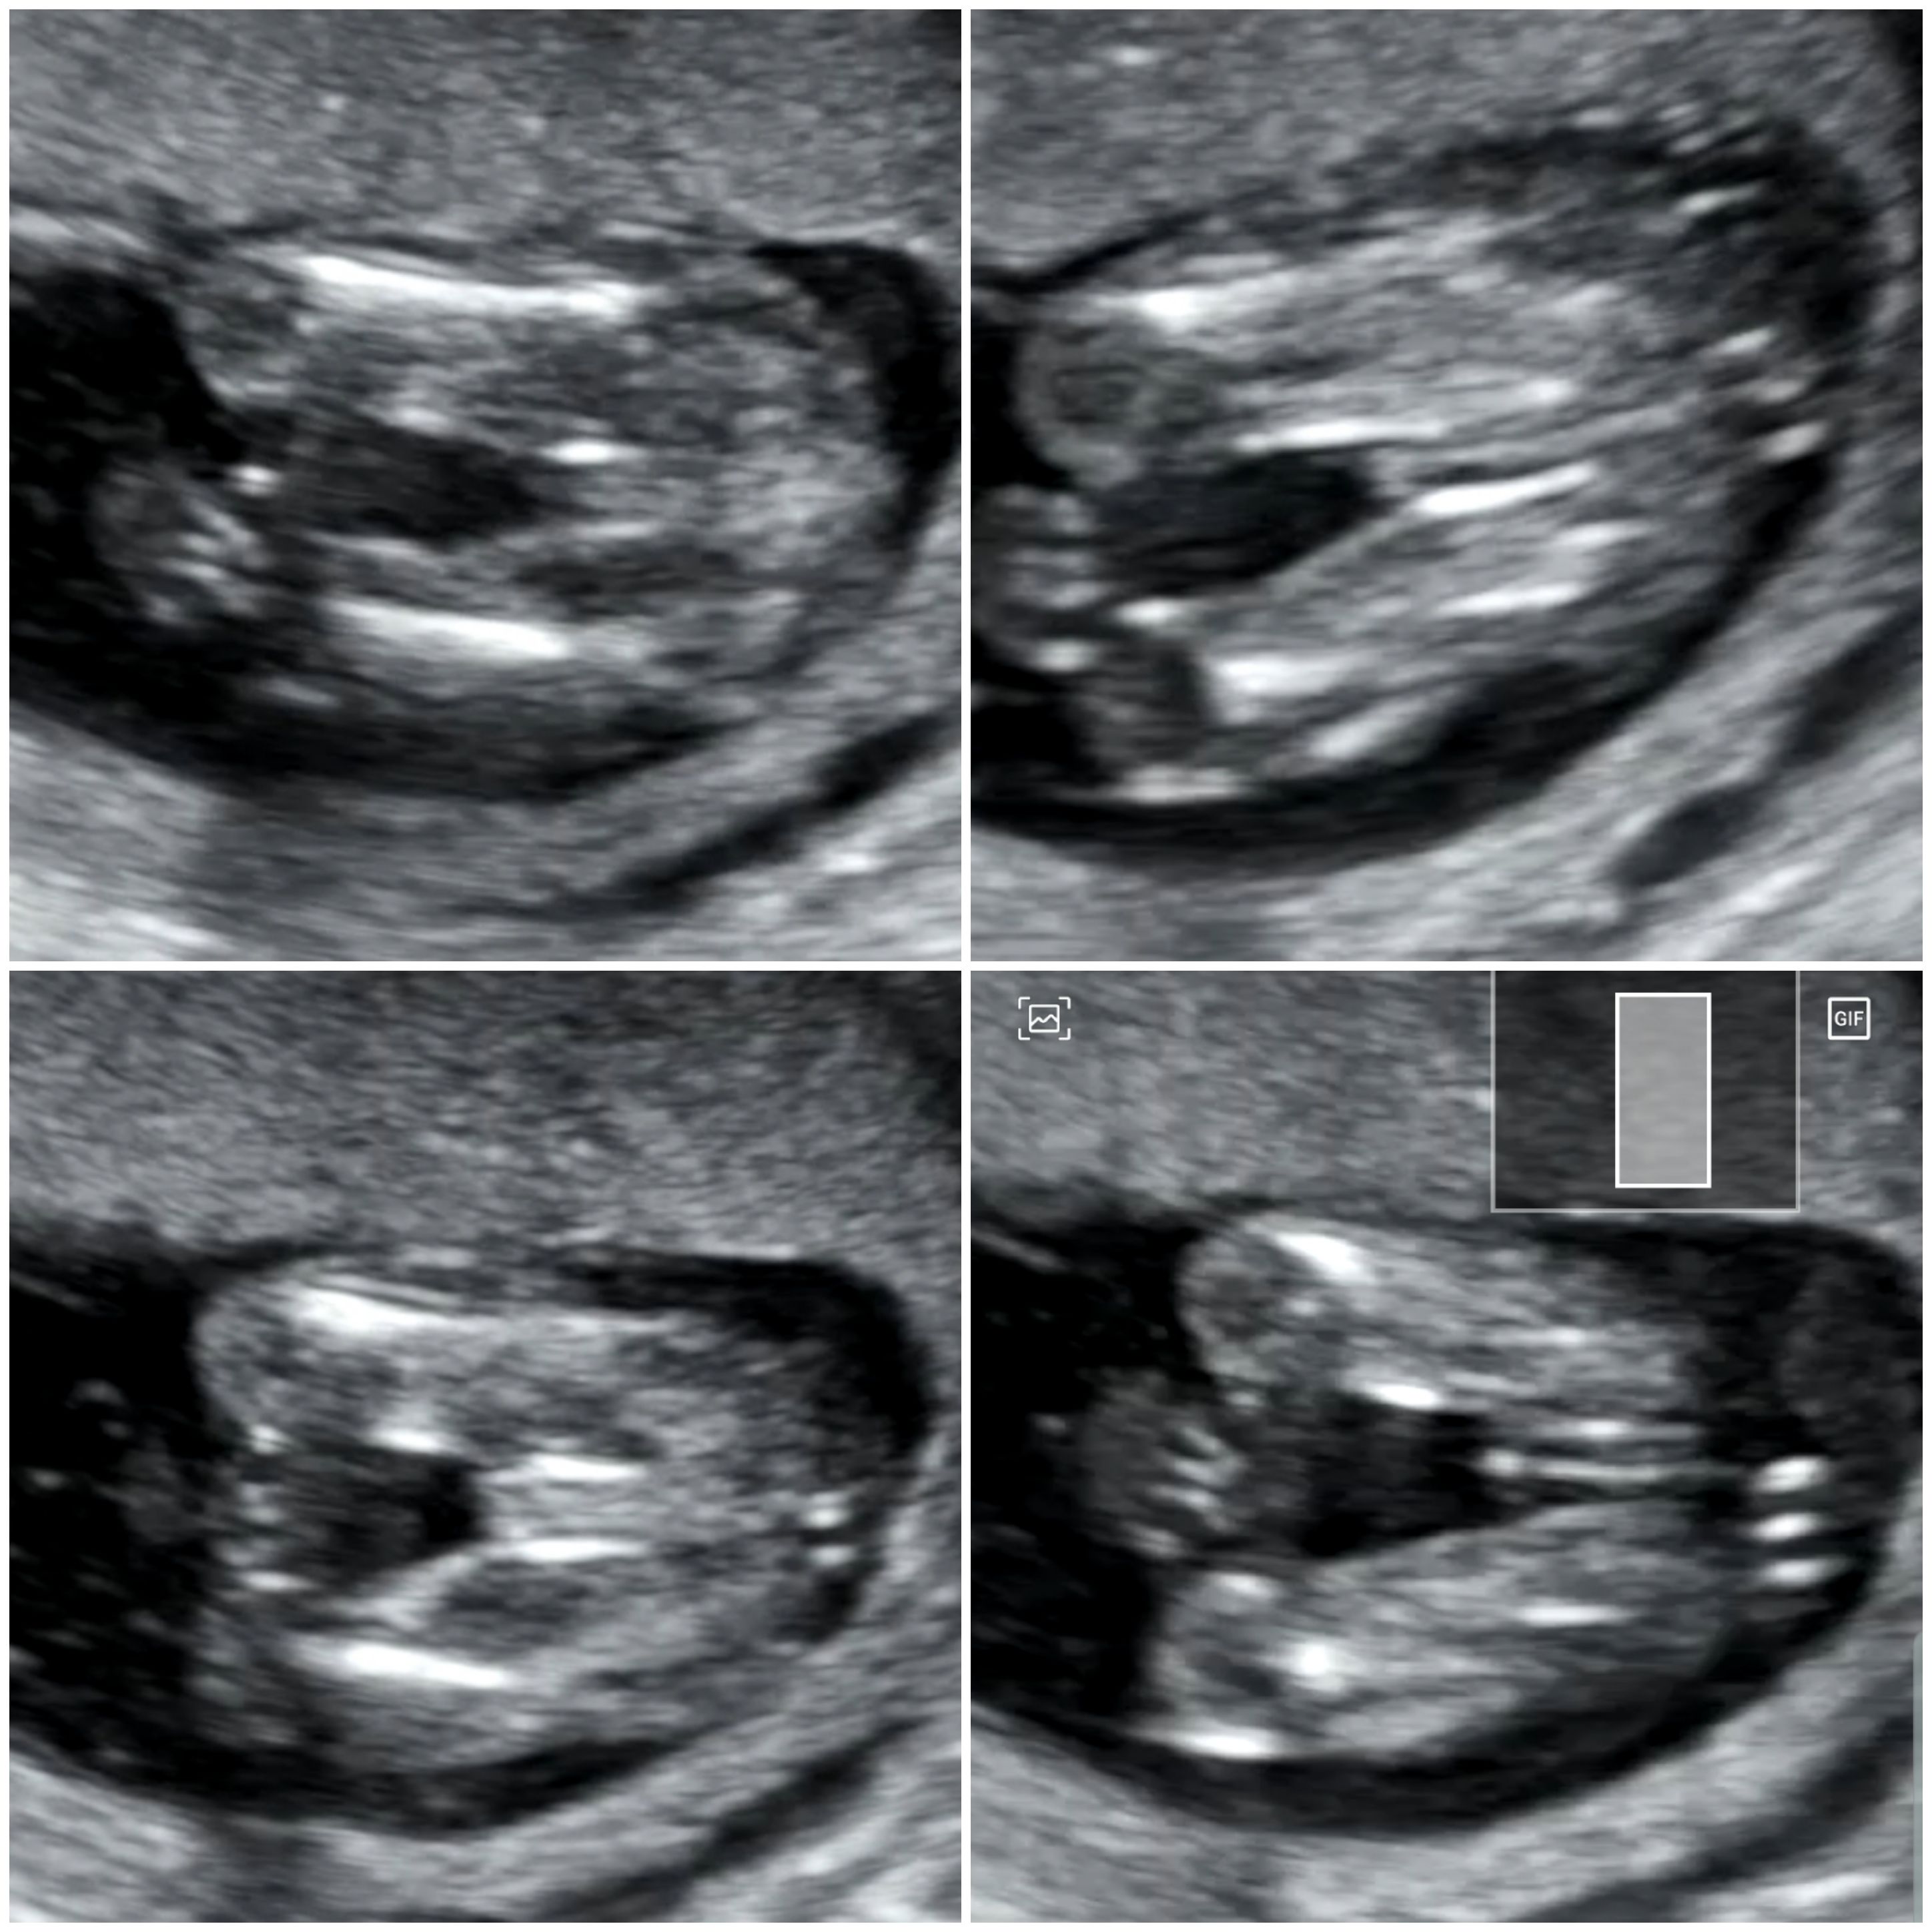

jakoś bylam tak zakręcona na wizycie ze ona po cytologii mi mowi prosze sie ubrać a ja mówię to usg nie będzie? I mówię ze chce aby sprawdzić czy dziecko urosło i czy wszystko ok. A ona no tak będzie ale przez brzuch przecież juz